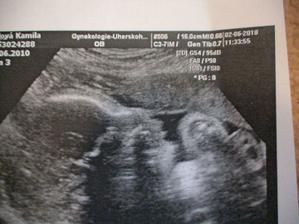

velký utz 2.6.(30tt+4) dopadl výborně, váhový odhad 1823g🙂 malá je hlavou dolů, obličejem na pravou stranu, dle hlavičky odpovídáme tt těhotenství, dle váhy jsme o týden větší🙂) placenta na zadní stěně. Doktor kontroloval srdíčko, ledviny, žaludek, páteř..měřil stehenní kost. ukazoval nám obličej na 2D utz-byly nádhreně vidět rtíky a nosík🙂 takže žádné rozštěpy nebo jiná nemilá překvápka🙂 a dostali sme i 3D fotečku. Sice jen půlku obličeje, pže plod vody už je ve 31tt méně, ale stejně je nááádherná🙂 Jo a pohlaví nám ukazoval, je tam děvčátko nad vší pochybnost🙂